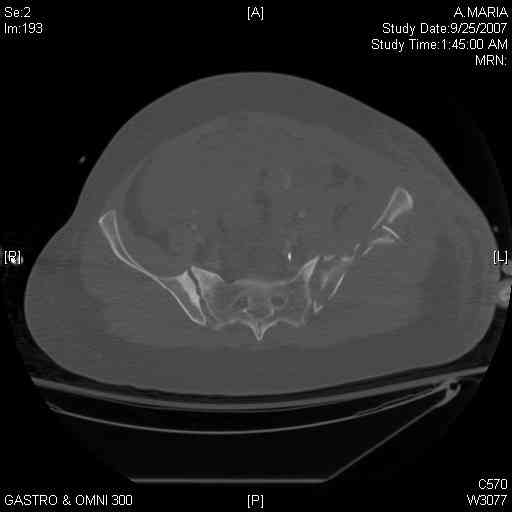

It's a comminuted iliac fracture involving the GS notch and all that

implies...use the lateral interval of an ilioinguinal, sequentially reduce,

and fix...if you want to, you can attach the dominant unstable fragment to

both the stable posterior iliac fragment and also to the anterolateral portion of the sacrum using plates...if you choose to anchor to both, the implants get congested on the iliac side of the SI joint so be precise with contouring and such applications...perhaps and based on the images shown, an iliosacral screw would only augment the construct if applied to the second sacral segment (but this is difficult to assess on the images shown). The crest components can be held securely with screws and/or peripheral plating.

Thanks. I probably didn't include enough images on the CT, but it didn't look to me like an SI screw would be of value except into S2, which I am not

comfortable placing. I will post finals if the neurosurgeons let me operate on her. ICPs still a problem.

I always manage these percutaneously. The basic idea is to peg the AIIS fragment to the crescent frag still attached to the sacrum.

But the reported results of open treatment are very good, so your plan of ORIF should yield acceptable results.